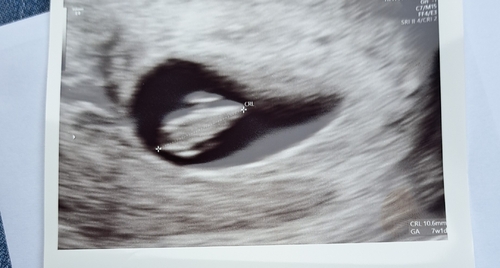

7 weken en 1 dag ! ;)

Volgensmij 7+1 hier 😊